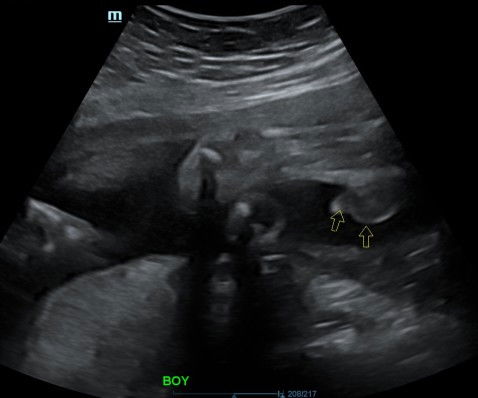

Hye mommy to be..esok 30/8 jmpa dr kk. baby da pusing dri usia kandungan 29w lgi..baby msuk laluan tu mcm mne yea?ap tnda dy adakh skit celah peha dan tulang pelvis sbb sy sdg alami skrg..ad x tips cepatkn bersalin 😅due date 15/9 tpi ramai tgok bersalin awal..sy firstmom xsbr pon ad tkut pon ad..sy doakn untuk mommy ii yg da nk bersalin semoga urusan kita semua dipermudahkan..selamat kedua"nya Amin"..#firstmom #firstbaby #ingintahu #bantusharing